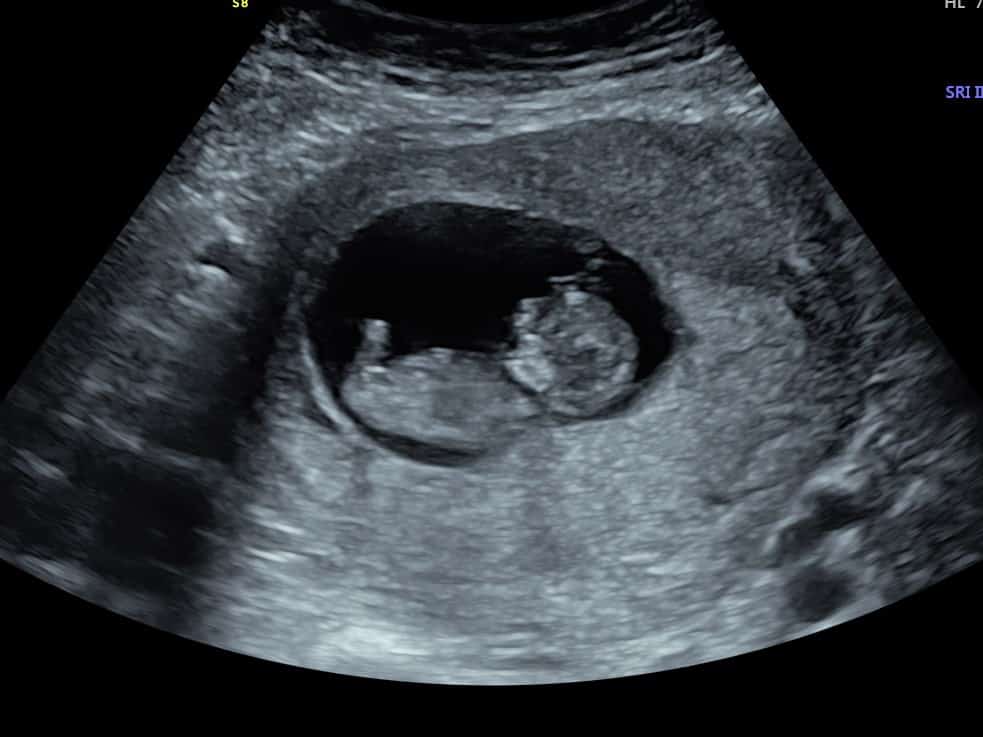

At 6 weeks, baby is only around 4mm so is very small. You’ll see a pregnancy sac, a yolk sac (which provides baby with all the nutrients they need until the placenta takes over, around week 10) and baby’s heartbeat.

The first thing the sonographer looks for is the position of baby. They will check the baby is in the uterus as it should be, rather than elsewhere which can be dangerous for mum. The sonographer will then look for the number of pregnancy sacs and babies to confirm a single or multiple pregnancy. The heartbeat is next; during your early pregnancy scan we do not listen to the heartbeat as it wouldn’t be safe for baby, but we will show you the heartbeat flickering on our screens.

Once the pelvic assessment is complete, the sonographer will return to your baby and measure their length from crown to rump (head to tail) to provide you with accurate dating.